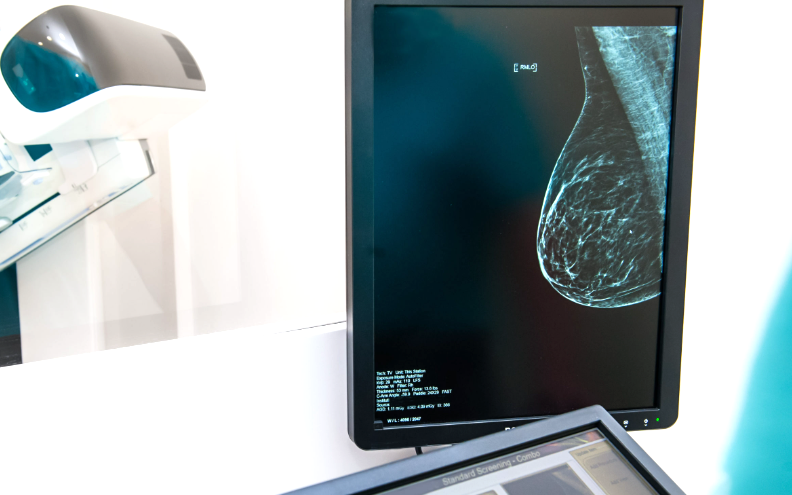

Как часто и в каком возрасте делать маммографию?

Маммография - это единственный эффективный инструмент скрининга (то есть тотального периодического обследования всех здоровых женщин в популяции), повышающий вероятность раннего выявления рака молочной железы и снижающий риск смерти от рака молочной железы на 20-40%. Риск заболеть никак не меняется, но благодаря ранней диагностике удается полностью вылечить от болезни существенно больше пациенток. Периодичность маммографии зависит от возраста и индивидуальных факторов риска. Для женщин без факторов высокого риска рака молочной железы периодичность маммографии следующая: Важно! Для женщин моложе 40 лет маммография не подходит для скрининга ввиду низкой диагностической точности (плотная ткань молочной железы не позволяет детально рассмотреть начальные проявления опухолевого процесса). Для женщин с факторами высокого риска рака молочной железы онколог назначает индивидуальный план периодического обследования. К факторам высокого риска рака молочной железы относятся: При наличии перечислен

Маммография - это единственный эффективный инструмент скрининга (то есть тотального периодического обследования всех здоровых женщин в популяции), повышающий вероятность раннего выявления рака молочной железы и снижающий риск смерти от рака молочной железы на 20-40%. Риск заболеть никак не меняется, но благодаря ранней диагностике удается полностью вылечить от болезни существенно больше пациенток.

Периодичность маммографии зависит от возраста и индивидуальных факторов риска. Для женщин без факторов высокого риска рака молочной железы периодичность маммографии следующая:

• для женщин 40-49 лет маммография рекомендуется один раз в 2 года;

• в возрасте 50 лет и старше рекомендуется ежегодная маммография.

Важно! Для женщин моложе 40 лет маммография не подходит для скрининга ввиду низкой диагностической точности (плотная ткань молочной железы не позволяет детально рассмотреть начальные проявления опухолевого процесса).